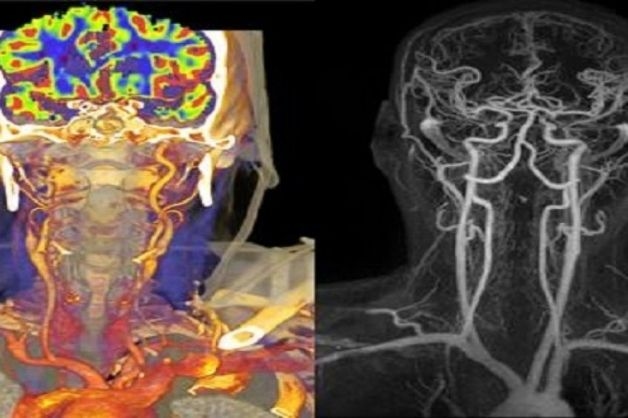

2.4 Chẩn đoán hình ảnh u não qua kỹ thuật chụp mạch máu não

Chụp mạch máu não sử dụng kỹ thuật chụp X-quang và phương pháp tiêm thuốc cản quang để xác định hình ảnh mạch máu bên trong não. Kỹ thuật này có thể tạo ra nhiều góc chụp khác nhau với nhiều tư thế để đánh giá vị trí, kích thước, số lượng mạch máu quanh khối u và mạch máu nuôi khối u.

Ngoài ra, kỹ thuật chụp mạch máu não còn giúp cung cấp thêm các thông tin về những bất thường tại não thông qua kỹ thuật chụp MRI và CT.

Chụp mạch máu não thông qua kỹ thuật chụp MRI và CT giúp đánh giá vị trí, số lượng mạch máu quanh khối u.